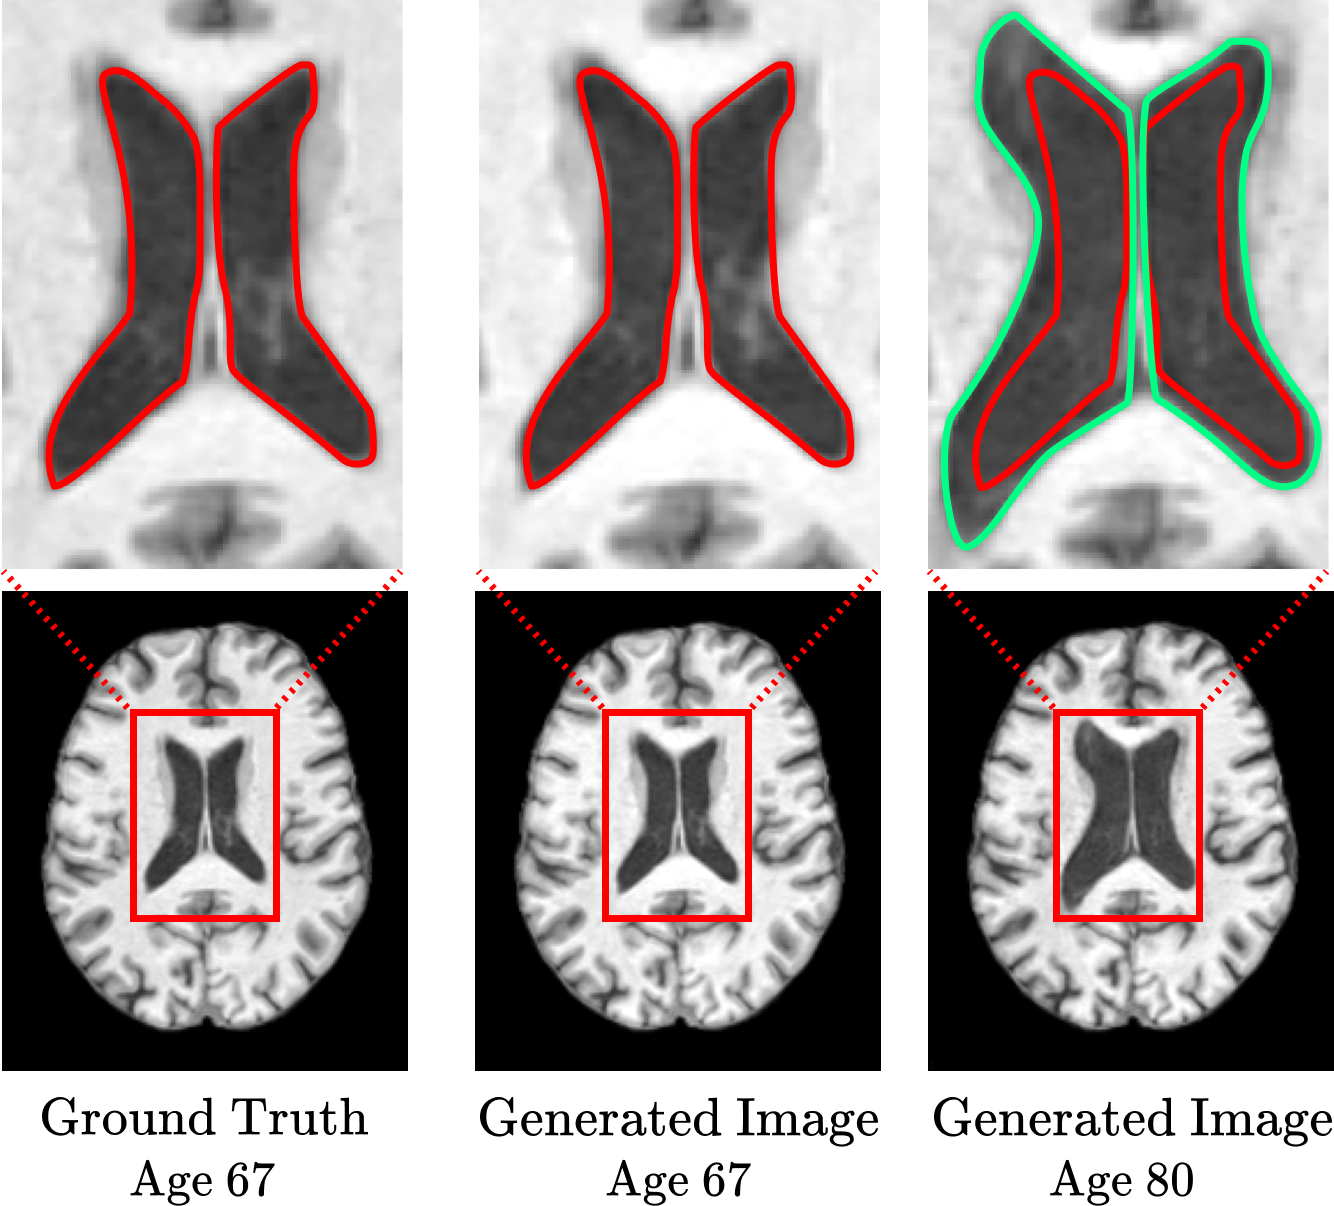

Lastly, for a more detailed comparison, we zoomed in on the ventricle areas of both the ground truth and generated images, as depicted in Fig. 6. The image synthesized with age 67 (middle) precisely matches the ventricular size in the ground truth (left), while the age-converted image to age 80 (right) shows an appropriately enlarged area. Through rigorous qualitative evaluation, we confirm that our proposed IdenBAT successfully performs age-appropriate transformations, simulating the aging process with a high level of identity preservation and accuracy.